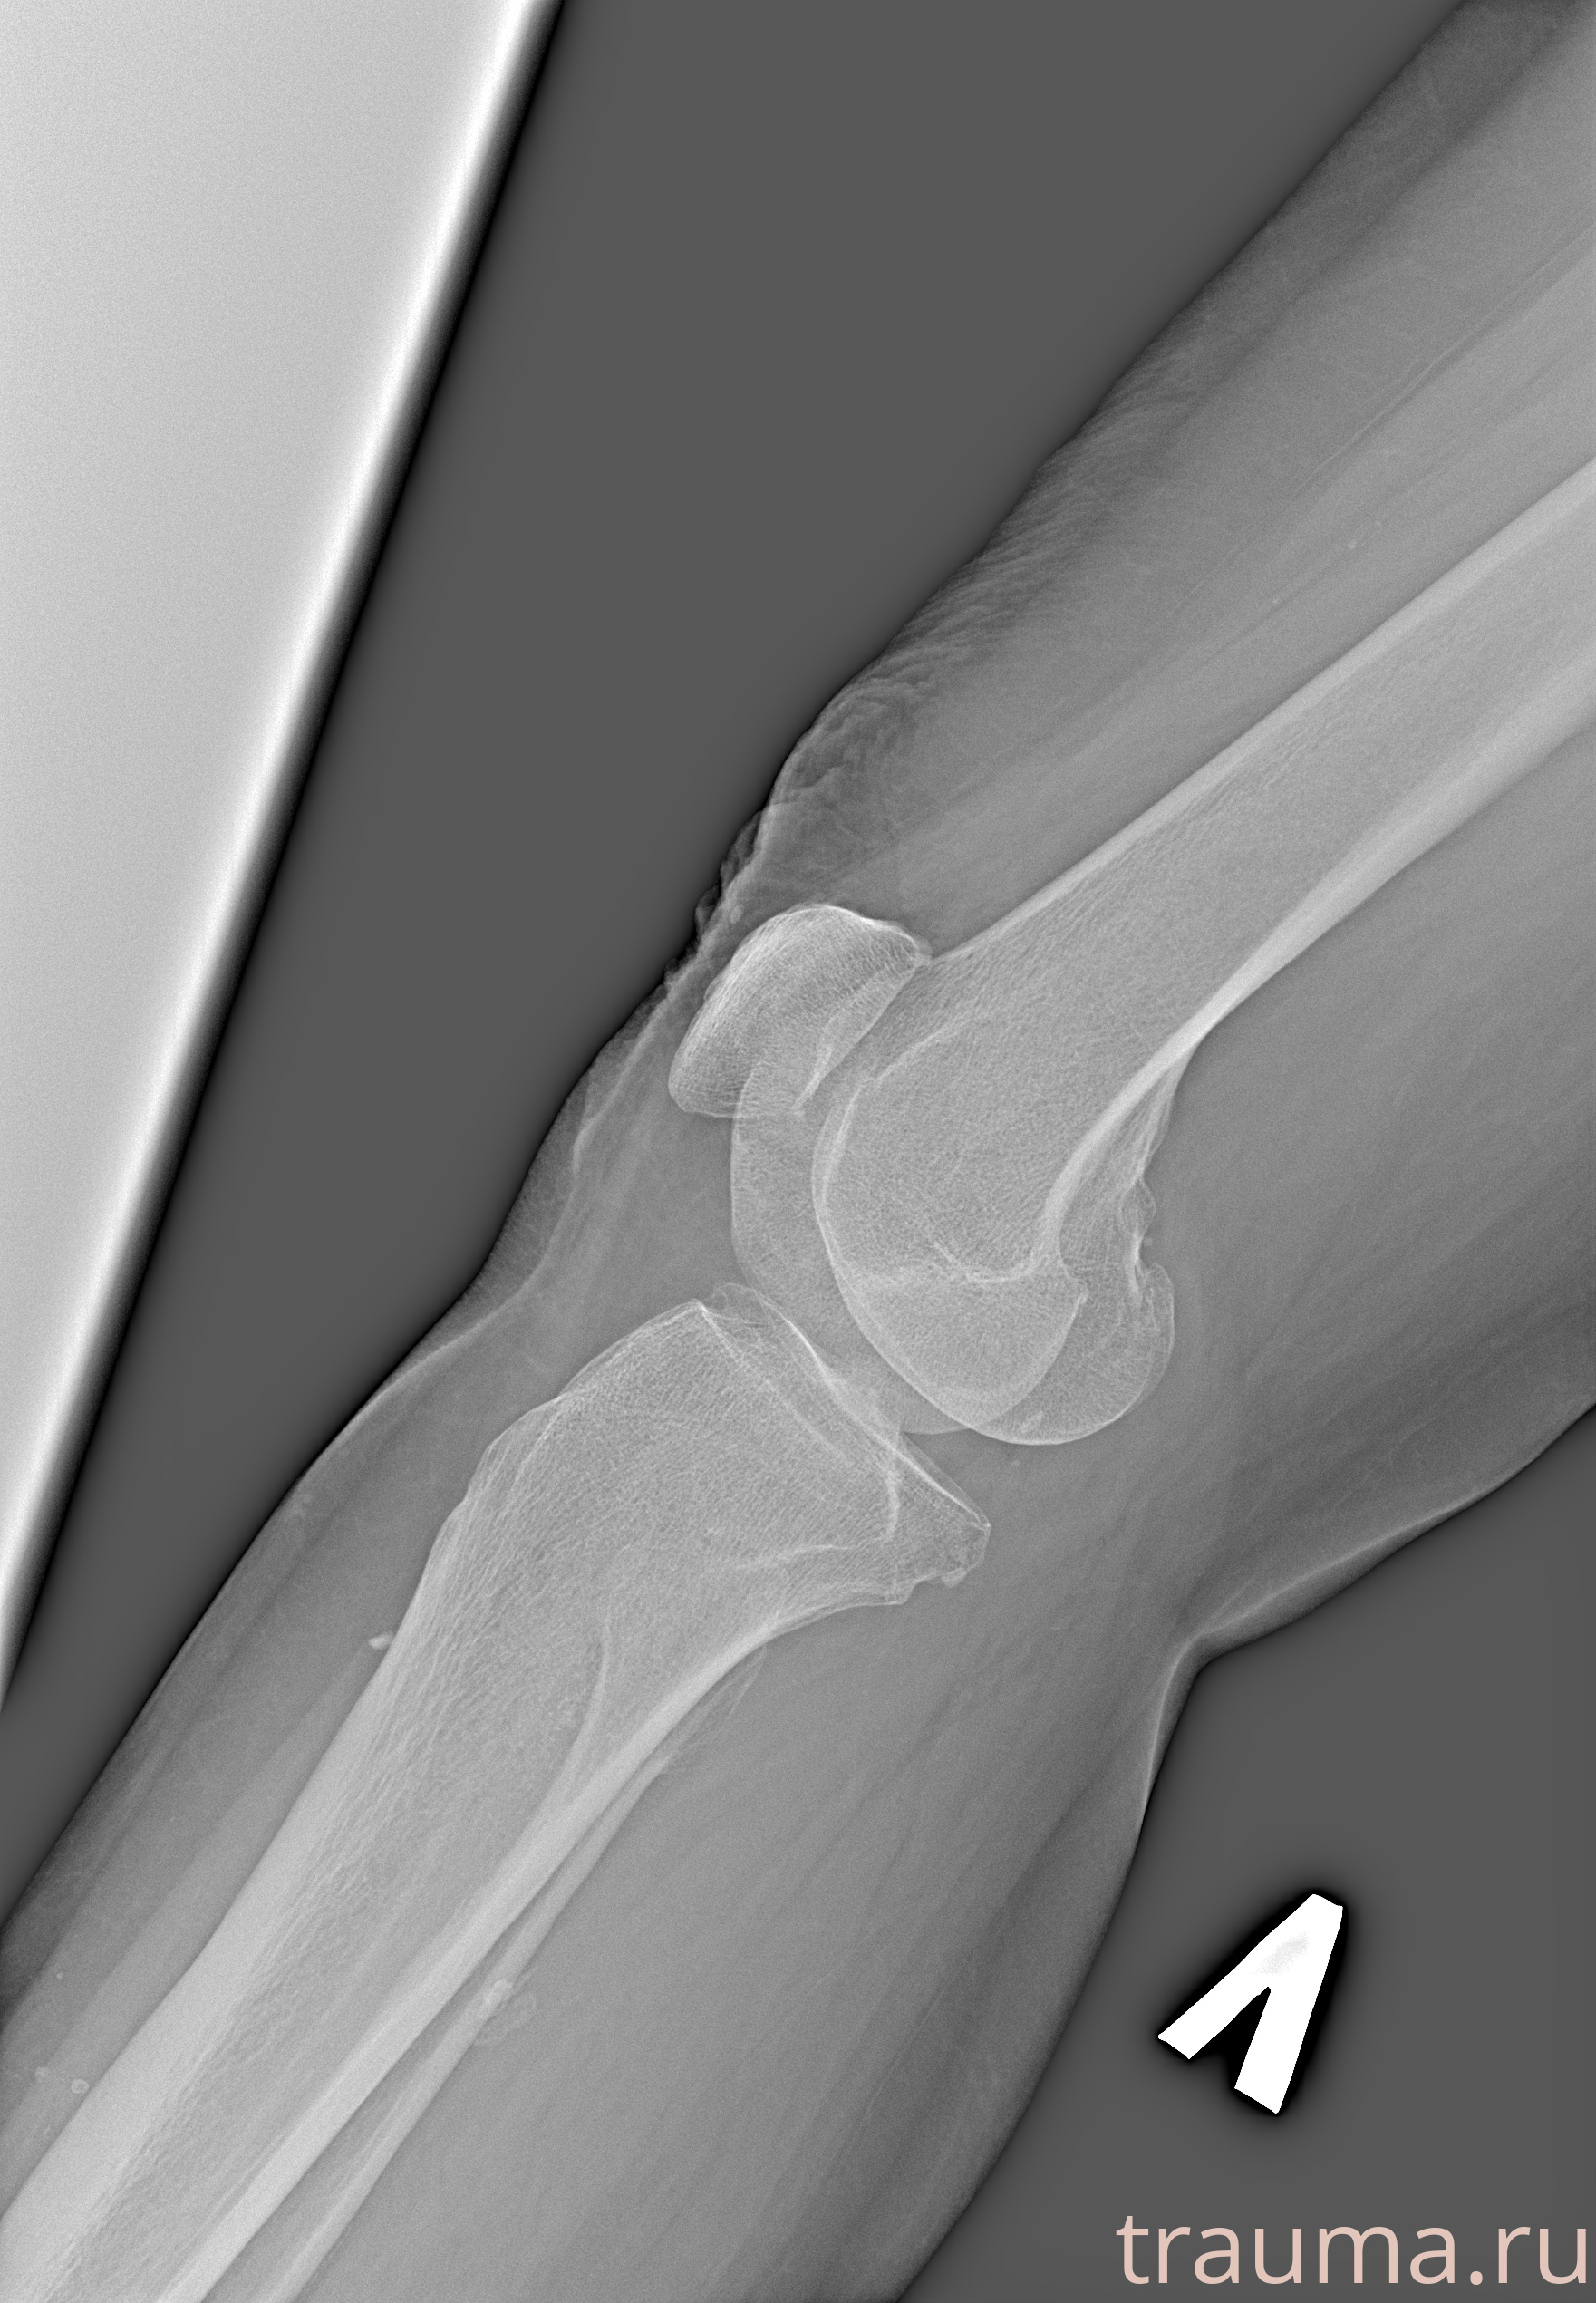

Рентген на дому: по вашему адресу приезжает врач-рентгенолог, травматолог-ортопед с мобильным рентгеновским аппаратом, проводит диагностику травмы или заболевания, делает необходимые рентгенограммы, дает рекомендации по дальнейшему лечению. Получить качественные снимки в домашних условиях возможно благодаря уникальной методике, разработанной МосРентген Центром для института  Склифосовского